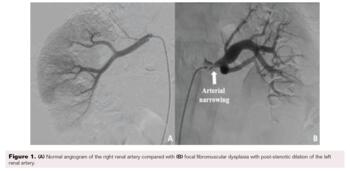

A 22-year-old man presented to the clinic with a new onset of elevated blood pressure ranging 130-150/80-90 mmHg. He denied a family history of hypertension, recent over-the-counter decongestant use, tobacco or illicit drug use, excessive alcohol intake, or a history of sleep apnea. His first elevated blood pressure was incidentally found 2 months earlier when he tested positive for SARS-CoV-2 and once more while donating blood plasma. The patient otherwise had no symptoms. He was started on amlodipine 10 mg once daily and telmisartan 80 mg once daily. At the 1-month follow-up, he continued to have unresolved hypertension, so chlorthalidone 25 mg once daily was added. His lab work showed renin activity elevated at 20 ng/mL/h with normal aldosterone. His metanephrine and thyroid-stimulating hormone/thyroxine levels were normal. His basic metabolic panel (BMP) showed elevated creatinine at 1.4 mg/dL and decreased sodium at 133 mmol/L but was otherwise unremarkable. A renal ultrasound Doppler revealed a normal proximal left main renal artery peak velocity at 105 cm/s; however, the mid-left main renal artery peak velocity was elevated at 312 cm/s, suggesting RAS. A computed tomography (CT) angiogram of the abdomen and pelvis showed smooth tapered narrowing at the proximal left renal artery, with peak narrowing measuring 2 to 2.5 mm in diameter approximately 8 mm distal to the ostium and at least moderate distal post-stenotic dilation. The remainder of the arteries, including an accessory artery to the right kidney, appeared to be normal bilaterally. The patient subsequently underwent angiography, which found discrete 80% stenosis in the left proximal renal artery and severe post-stenotic aneurysmal dilation (Figure 1). The right renal artery angiography was normal. Intravascular ultrasound showed no atherosclerotic plaque, web plexus, or calcification in the left renal artery (Figure 2). Balloon angioplasty of the left renal artery was performed using a 0.014" Hi-Torque All-Star guidewire (Abbott) and a 6 mm Viatrac balloon (Abbott) at 7 atm max pressure. An I.V. ultrasound was done using an Eagle Eye Platinum catheter (Philips). Post-intervention residual stenosis was noted at 20%. The patient was placed on aspirin 81 mg daily and clopidogrel 75 mg daily for 3 months. On a subsequent follow-up, the patient showed significant blood pressure improvement, and his medications were gradually stopped. His blood pressure normalized to 115–120/80 mmHg, and repeat lab values showed an unremarkable BMP and urinalysis.